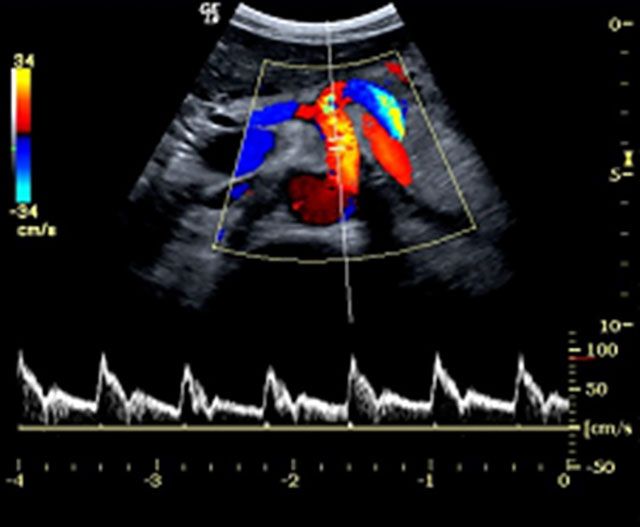

Το κέντρο διαθέτει τον υπερηχογράφο το LOGIQ E9 XDclear R6 του οίκου GE HEALTHCARE καθώς και το Siemens Acuson 2000. Το Siemens Acuson 2000 είναι εξοπλισμένο με ηχοβόλο κεφαλή active array, συχνότητας 6.0-18 MHz, η οποία έχει ειδική ανατομική κατασκευή για τη μελέτη του μαστού και real και static time 3D (στατική τρισδιάστατη απεικόνιση) και 4D (ζωντανή τρισδιάστατη απεικόνιση σε πραγματικό χρόνο).

Με τη χρήση της κεφαλής αυτής επιτυγχάνεται ο εντοπισμός και διάγνωση μικρών όγκων, καθώς και η ανίχνευση ανώμαλων νεόπλαστων αγγειακών δομών. Ενσωματώνει τη μοναδική επαναστατική πλατφόρμα υπερηχοτομογραφίας Truscan, η οποία καθιστά δυνατή την αποθήκευση των αυθεντικών ακουστικών δεδομένων (digital raw data) για πλήρη και πραγματική μεθ’ επεξεργασία των διενεργούμενων εξετάσεων, ώστε να δίδεται η δυνατότητα στον ιατρό να μελετά διεξοδικά τις υπερηχογραφικές εικόνες σε δεύτερο χρόνο, χωρίς να επιβαρύνεται και να ταλαιπωρείται ο ασθενής.